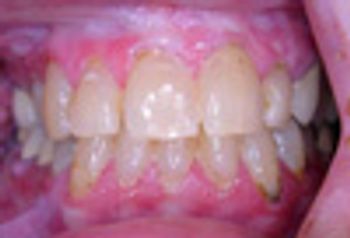

Contact stomatitis can occur as a result of cinnamon exposure. The condition can easily be managed by withdrawal of the antigen. A short course of systemic corticosteroid can produce dramatic improvement if symptoms are severe.

A 52-year-old woman presents with severe intra-oral ulceration and oral pain. She reports that several years earlier, she had been taking cephalexin when severe intra-oral ulceration developed.